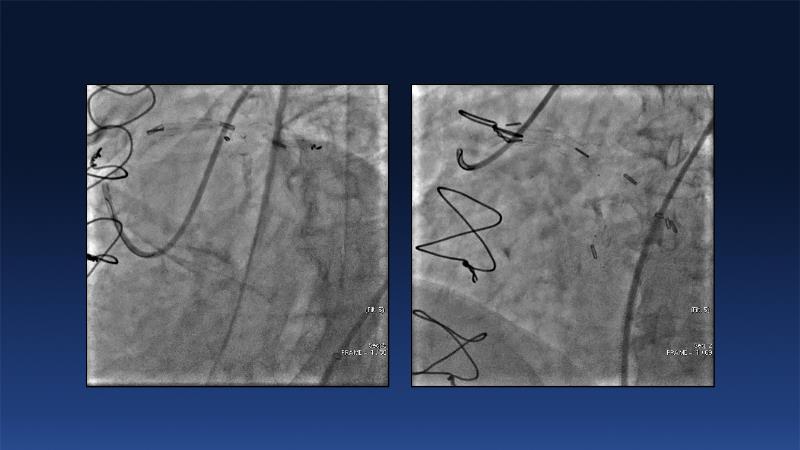

Revolutionising coronary calcium treatment: unleashing the potential of intravascular lithotripsy

Over the last five years, we have learned that there is a new tool for treating calcium, the greatest enemy of interventional cardiology, which can take various forms: intravascular lithotripsy. In this session, look at how to master this technique in different scenarios, from eccentric calcified lesions to left main bifurcations.